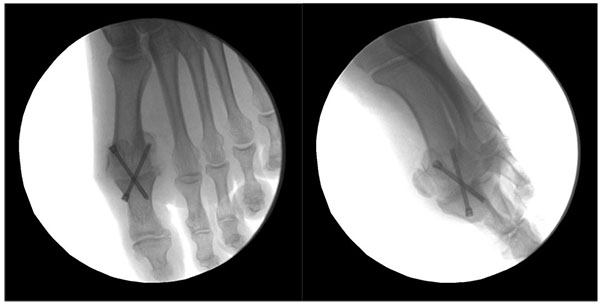

Fig. (5) Arthrodesis fixation.